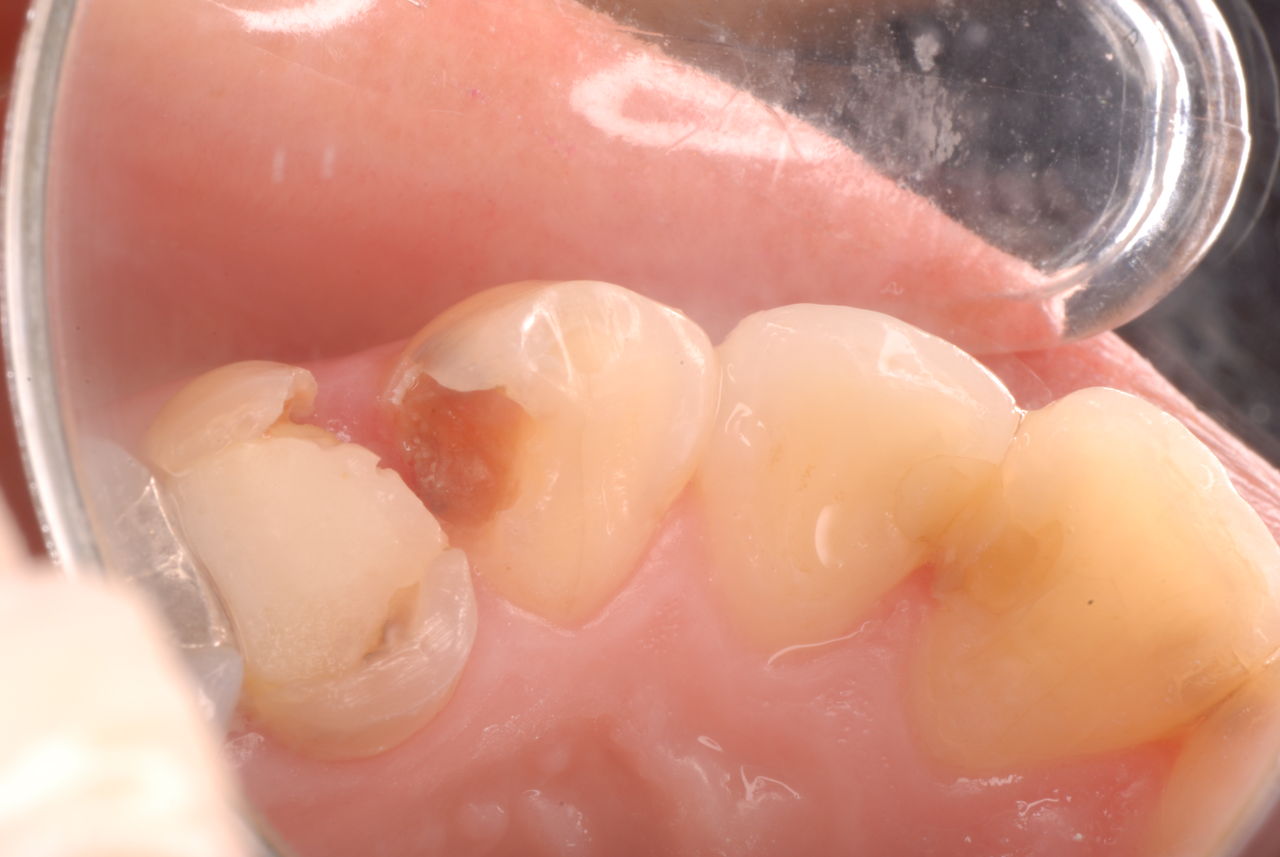

入れ歯の話から入りました。色々不満で注文があるようです。でも話が一段落して口腔内を調べると殆どの歯が重症で抜けそうな歯だらけなのです。

なぜ病気になるのかわからない方が多すぎます。歯が抜けるのは病気だからです。病気を治さずに何かお口の中に入れても土台である歯が抜けてしまっては同じことなのです。

何故歯が悪くなるのか、歯周病で抜けるのか分からなければ何を入れても歯は悪くなり抜けていくのです。

病気を治しましょう。それから差し歯や入れ歯を入れましょう!物を入れれば入れるほど、磨き方や掃除の仕方が上手にならなければ、すぐ抜けてくるのです。